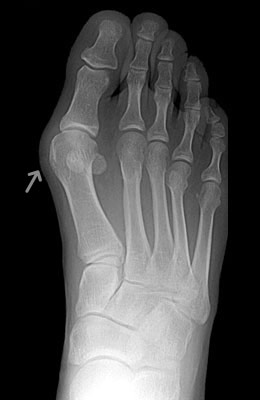

Before

After

Lapidus Forever Bunionectomy™

In this Lapidus procedure, the joint behind the great toe joint, the 1st metatarsophalangeal joint, is fused together with the bunion in a more corrected position. Notice the improved alignment of the great toe joint. 2 screws were used to fixate the bones together and facilitate it towards fusion.